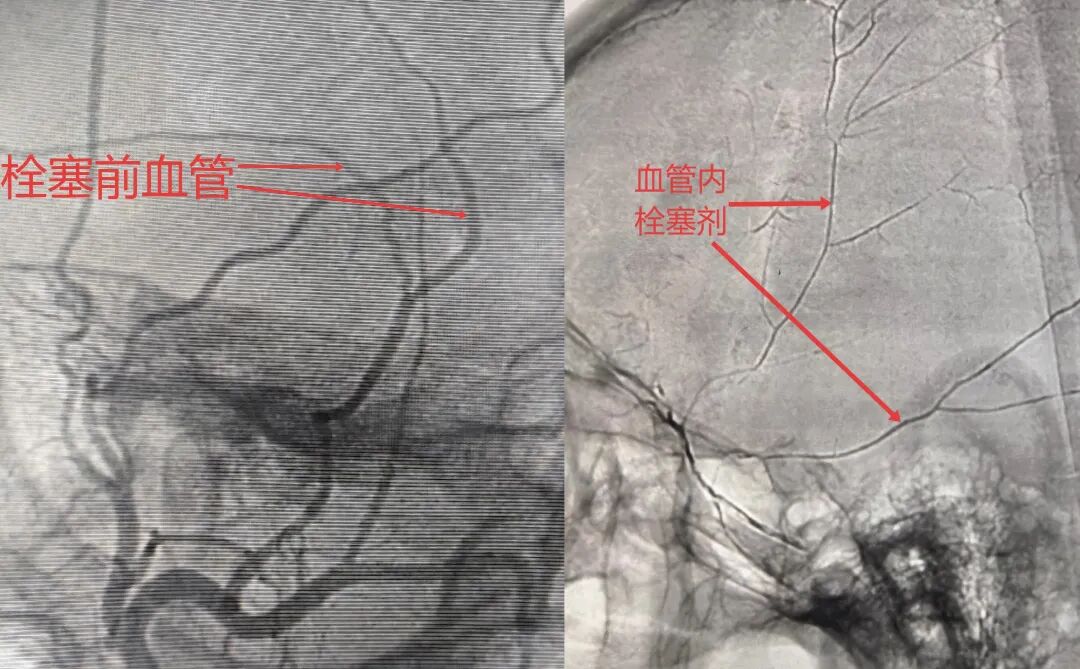

脑膜中动脉栓塞术的创新之处在于从源头解决问题,通过阻断病理性血管的血流,使血肿包膜逐渐萎缩,从根本上减少血肿的进展和复发,整个治疗过程无需开颅,只需在局麻或全麻下从股动脉或桡动脉穿刺细的导管,微导管沿着血管一路导航到头颅的硬脑膜中动脉中,使用栓塞剂堵塞其主干及分支即可。